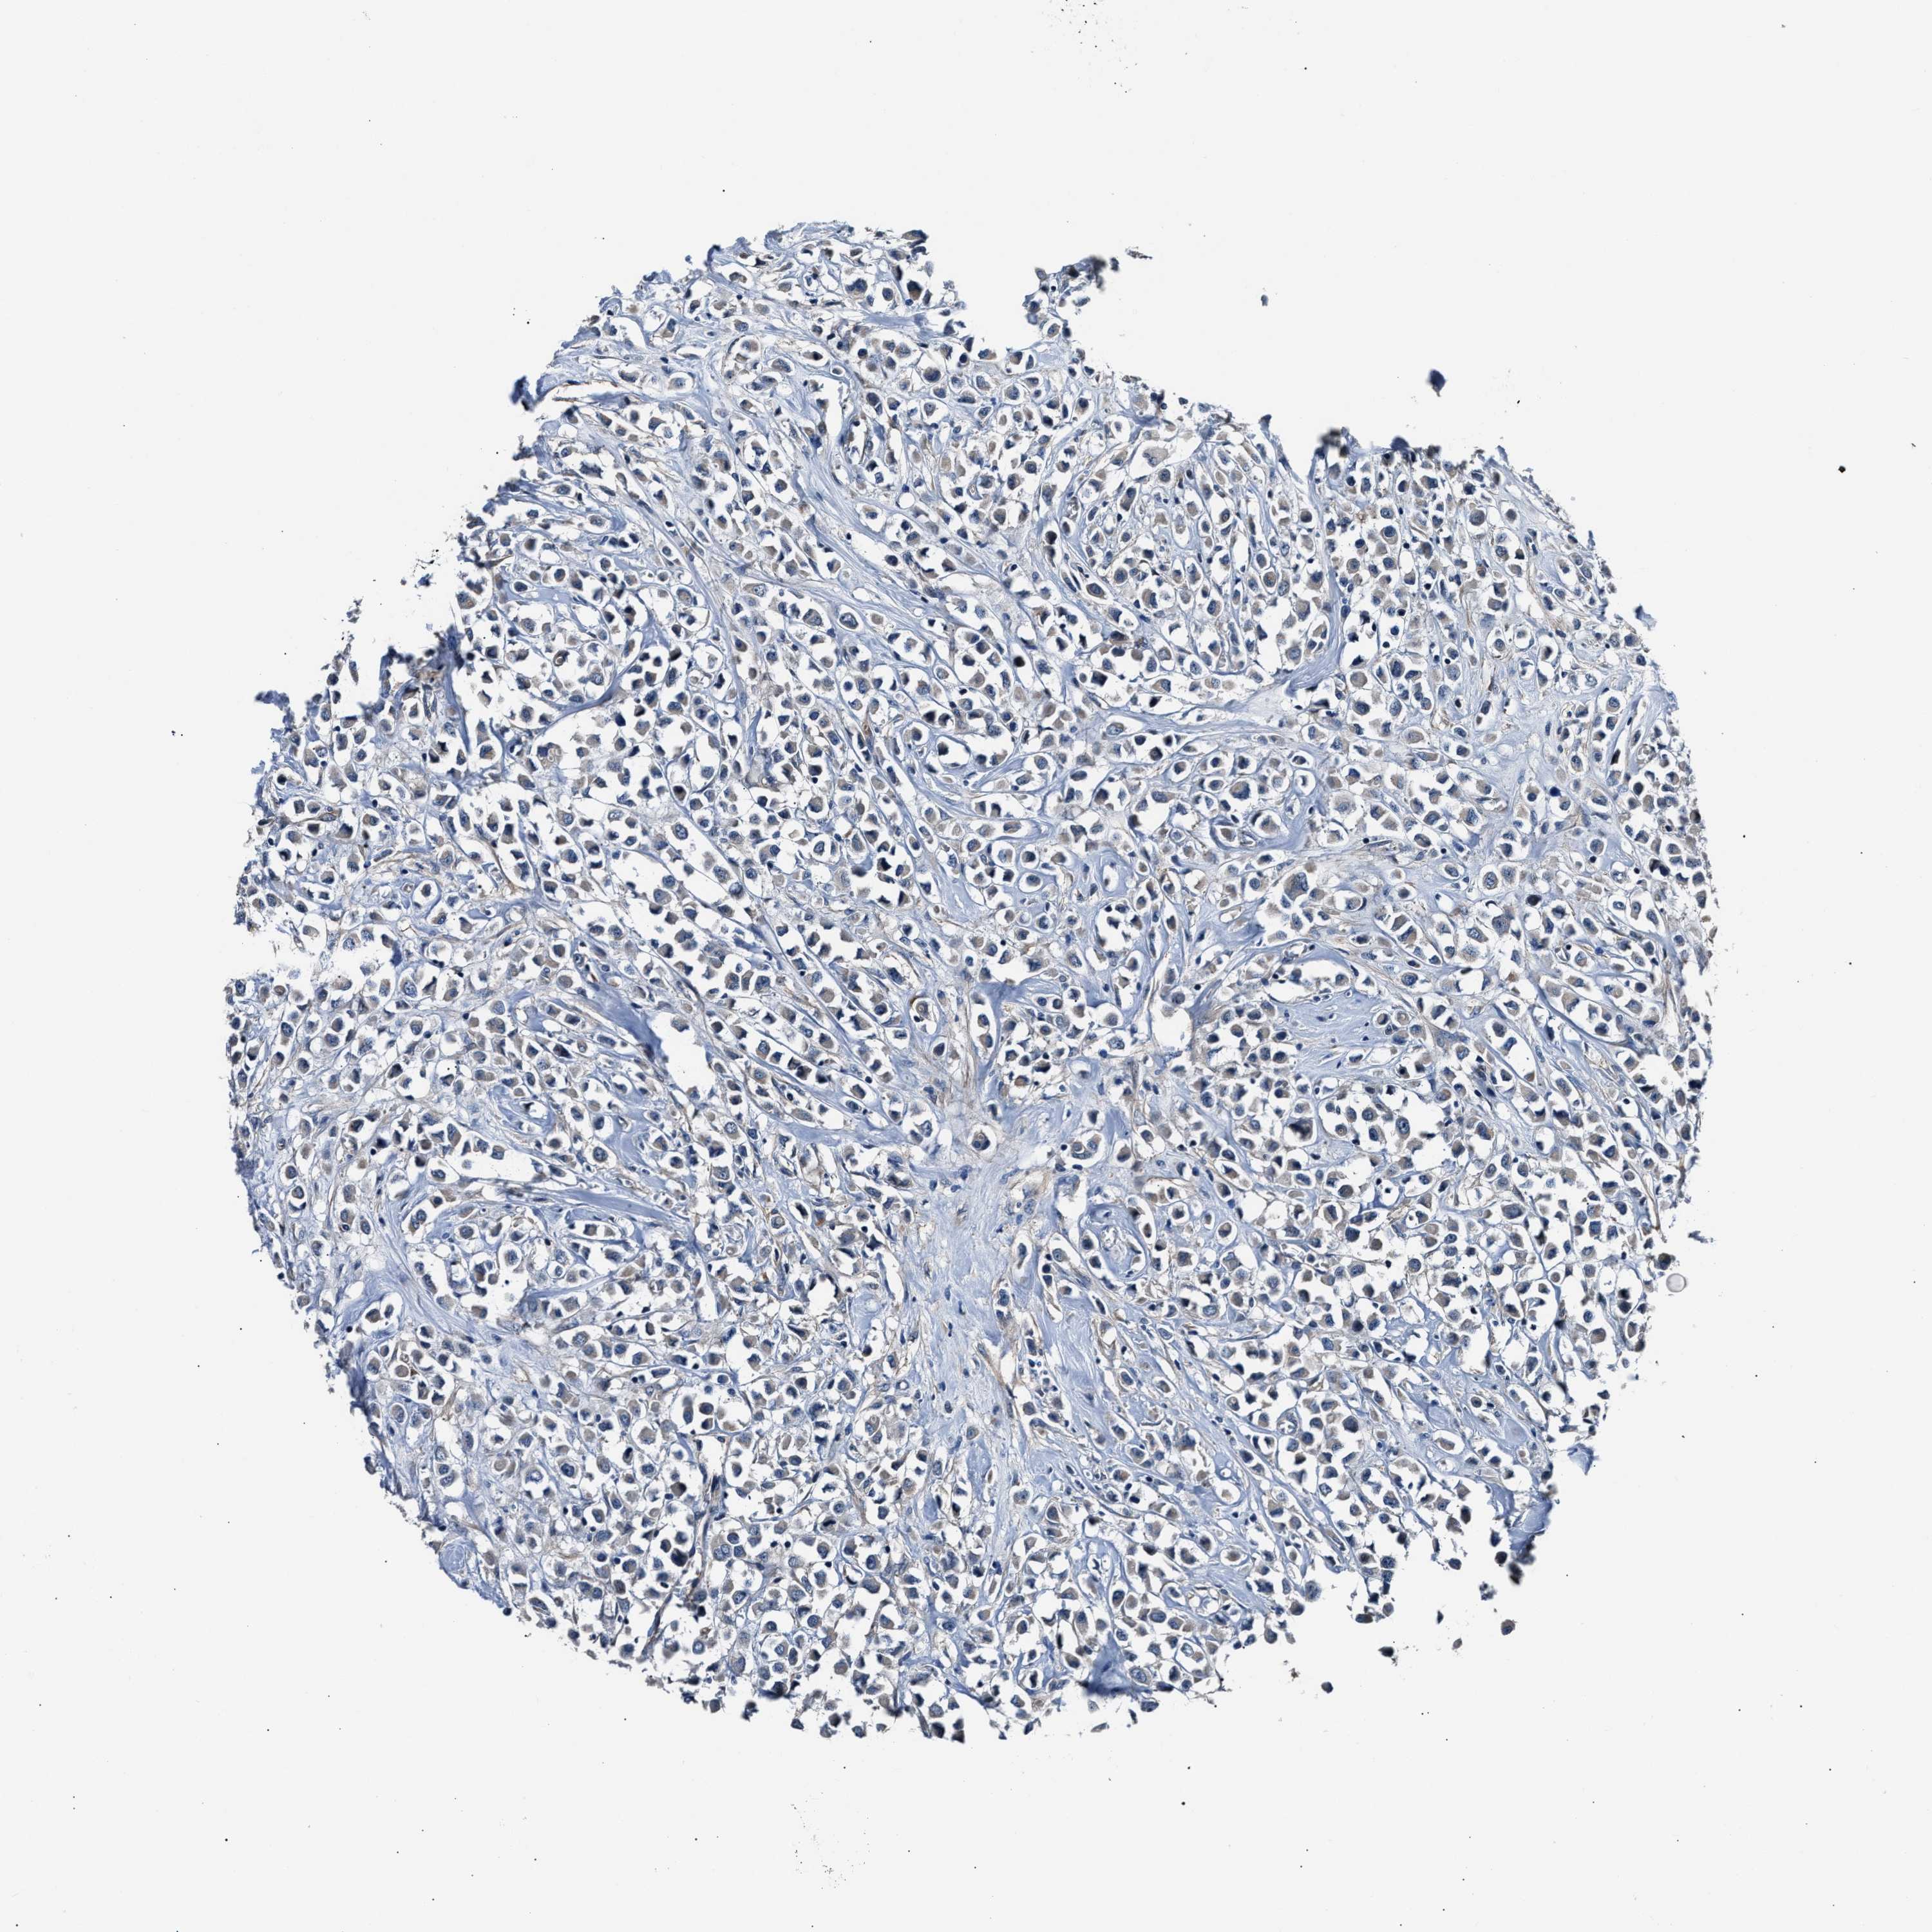

CANCER BREAST CANCER Show tissue menu

Breast cancer

Human cancer